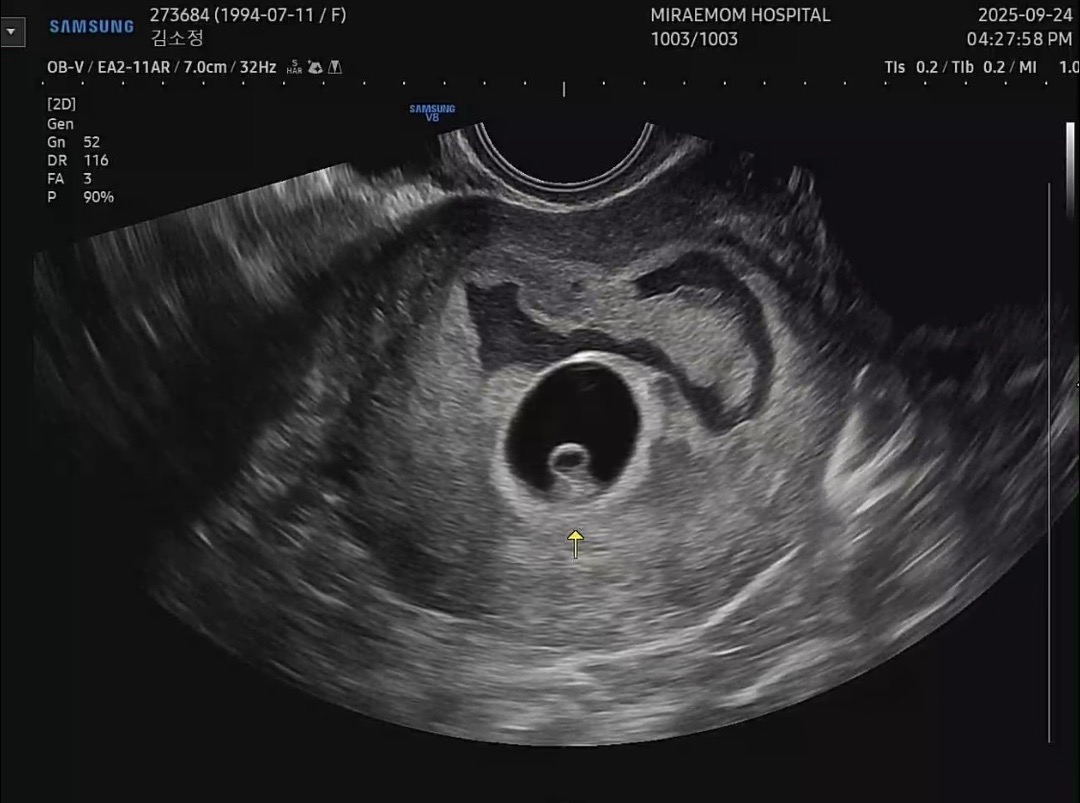

저번주엔 아기집만보고 아기집 옆에 피고임이 있어서 질정 일주일 넣고 이번주에 병원가니 난황도보고 아기심장소리도 들었어요 근데 피고임이 위로 이동하고 면적이 엄청 넓어져서 너무 걱정되요ㅜㅜㅜㅜ 피고임 컸는데 다 흡수되신 선배님 계실까요ㅜㅜ

9주일때 빨간피가 소변보는것처럼 줄줄 흘러서 응급실 갔더니 피고임 면적이 넓다고 했어요. 그러고 이틀뒤에 똑같은 상황. 타이유 주사 매일 맞고, 프롤루텍스2대, 질정제 처방았어요. 무조건 누워있으라는건 아니지만, 잘 쉬어주고 무거운거 들지말고 운동도 당분간 쉬라했어요. 현재 피고임 작아졌고, 아기는 3개월이에요. 피비침 없으면 너무 걱정 안해도 된다 했어요.